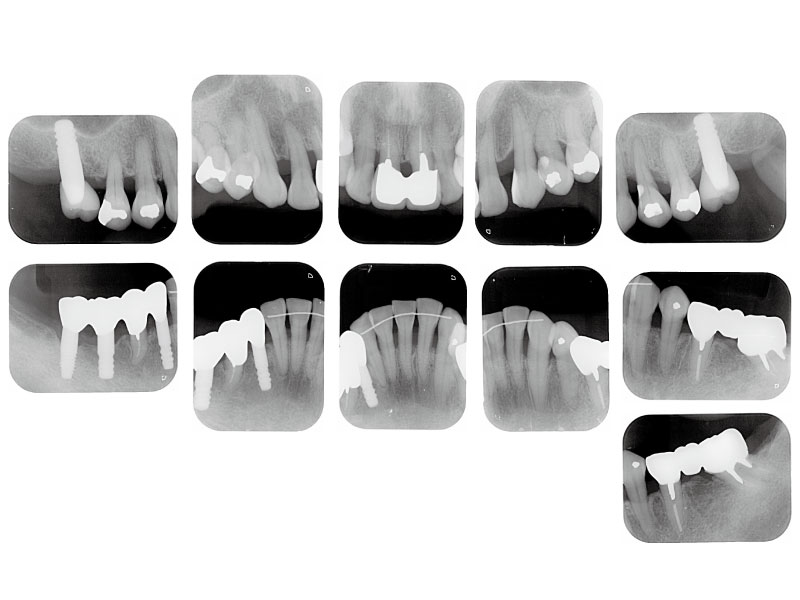

治療後X線写真